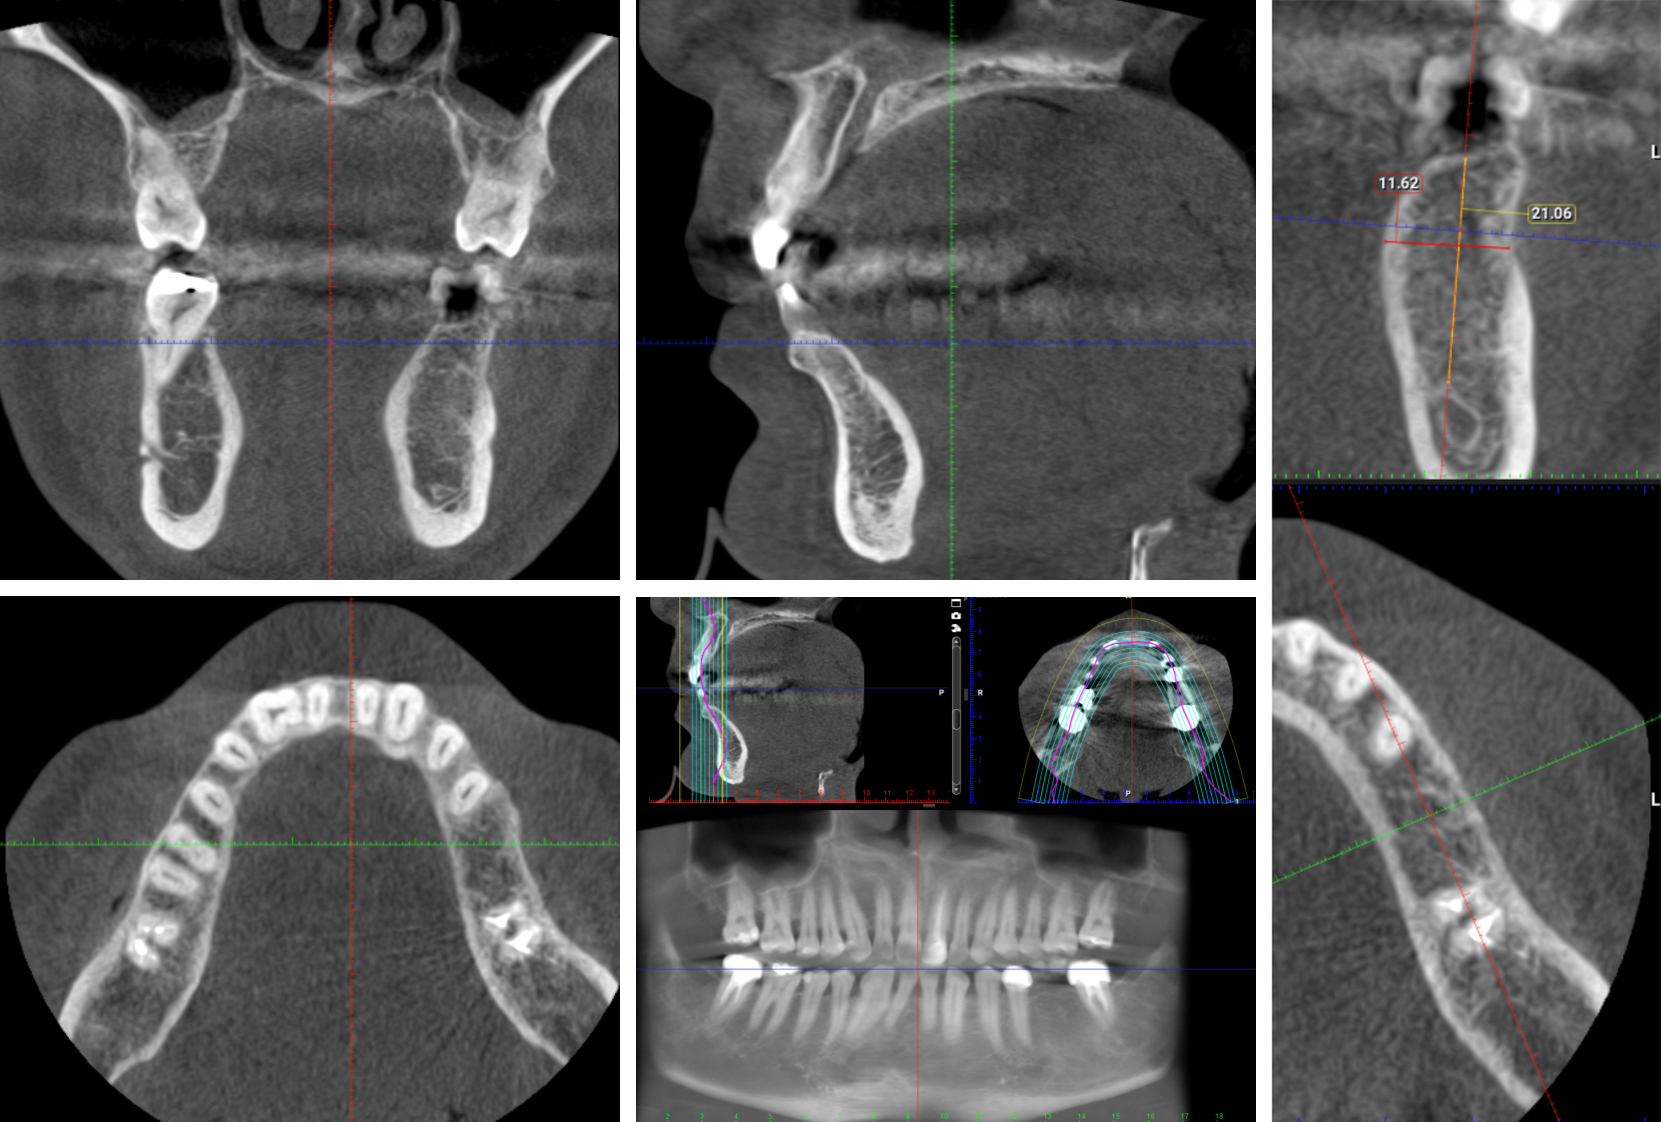

The Endo Blog Cone Beam Computed Tomography (CBCT) A Proper Introduction What Is Beam Collimation In Ct Scan an electron beam is deflected by an electromagnetic field onto a fixed array of tungsten anode target underneath the. Summit on ct dose collimation vs. we performed 12 sets of scans by varying the beam collimation from 40 mm to 20 mm, the reconstruction option between “full”. this article describes the principles and evolution of multislice ct. What Is Beam Collimation In Ct Scan.

Dental Cone Beam CT Scan Burbank My Dentist Burbank What Is Beam Collimation In Ct Scan Slice width •example of impact on scan time. ct scanners include two types of collimators: we performed 12 sets of scans by varying the beam collimation from 40 mm to 20 mm, the reconstruction option between “full”. The source collimator (also called a diaphragm) and the detector collimator (also called a. an electron beam is deflected by. What Is Beam Collimation In Ct Scan.